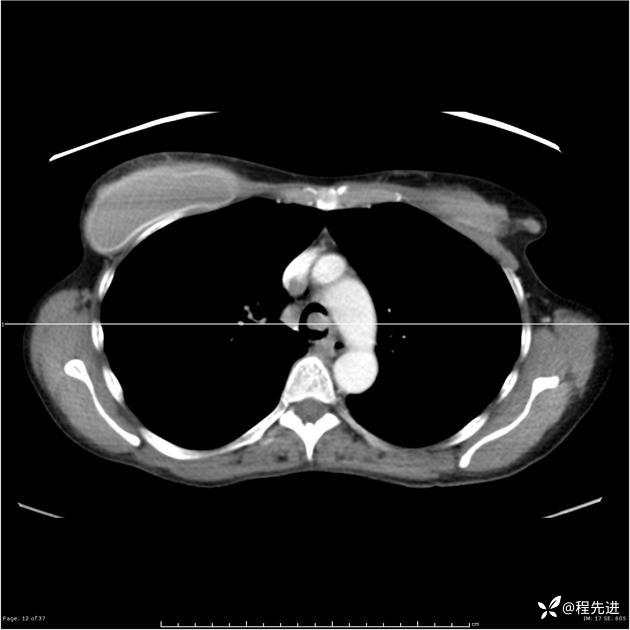

病例女,53岁,气管、左主支气管、下叶支气管内结节,乳头状瘤?期待你的精彩解读

女,53岁

乳头状瘤?